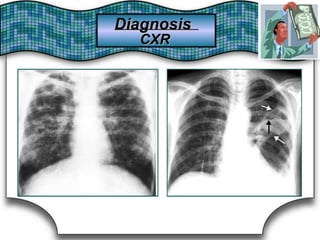

Chest X Ray (CXR)X Ray (CXR)Chest

Chest RadiographRadiographChest Suggestive DiagnosisSuggestive Diagnosis

Cardiomegaly, increasedincreasedCardiomegaly,

pulmonary vascular distributiondistributionpulmonary vascular

Chronic heartheart failure,failure, mitralmitral valve stenosisvalve stenosisChronic

Cavitary lesionsCavitary lesions Lung abscess, TB,TB, necrotizing carcinomanecrotizing carcinomaLung abscess,

Diffuse alveolar infiltratesinfiltratesDiffuse alveolar Chronic heartheart failure,failure, pulmonary edema,pulmonary edema, aspirationaspirationChronic

Hilar adenopathy oradenopathy or massmassHilar Carcinoma, metastaticmetastatic disease,disease, infectioninfectionCarcinoma,

HyperinflationHyperinflation COPDCOPD

Lobar oror segmentalsegmental infiltratesinfiltratesLobar Pneumonia, thromboembolism, obstructing carcinomathromboembolism, obstructing carcinomaPneumonia,

Mass lesion,lesion, nodules,nodules, granulomasgranulomasMass

Carcinoma,

granulomatosis,

metastatic disease, Wegener's

vasculitides

Carcinoma, metastatic disease, Wegener's

septic embolism,granulomatosis, septic embolism, vasculitides

Patchy alveolar infiltratesinfiltratesPatchy alveolar

Bleeding disorders, idiopathic pulmonaryBleeding disorders, idiopathic pulmonary

hemosiderosis, Goodpasture's syndromesyndromehemosiderosis, Goodpasture's